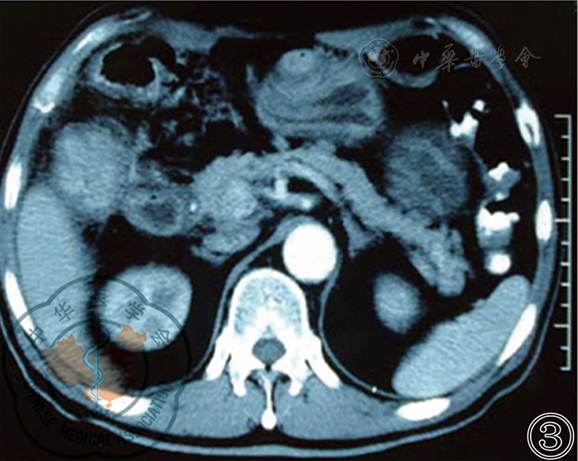

图2 术前CT检查示结肠肝曲肿瘤侵犯胰头十二指肠

图4 新辅助治疗后CT检查示结肠肿瘤仍与十二指肠关系密切